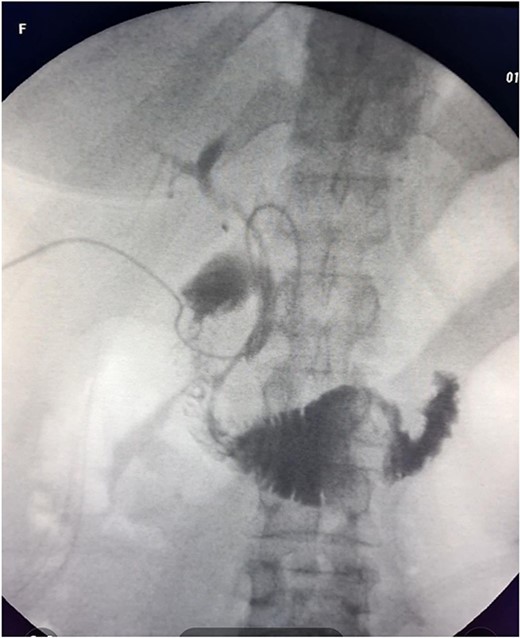

The patient was scheduled for a laparoscopic cholecystectomy the following day. Intraoperatively, an enlarged gallbladder hydrops with the presence of various caliber calculi in the lumen, the largest of which measured 2 cm/d, was found. The contents of the bladder are punctured and evacuated to facilitate its grasping in the fundus area and creating a good exposure of Callot’s triangle. Using a four trocar technique, a dissection was performed in the triangle of Callot, noting the difficult manipulation in the area between cystic duct and common hepatic duct. The cystic duct is identified to its confluence with the common bile duct at a 45° angle. The cystic artery was also visualized, after which clips were placed on both structures after ensuring that they entered the gallbladder. Dissection of the gallbladder in its distal part, attached to the liver parenchyma above Rouvier’s line, was started using electrocautery and hook. The tissue density of a limited area in the distal part between the wall of the gallbladder and the liver parenchyma was dissected using a hook. A bile duct was opened in its unusual anatomical location (Fig. 1). Due to lack of equipment for intraoperative cholangiography, it was converted to open access and subsequent revision of the extrahepatic bile ducts. The common bile duct and right–left hepatic duct were mobilized to the site of entry into the liver parenchyma. A parietal lesion of the right hepatic duct just above the confluence and anatomical integrity of the common bile duct and left hepatic duct were found. After examining the removed gallbladder, it was found that it was immediately flowing into a duct which connects the cystic duct with the right hepatic duct as depicted in Fig. 2. A plasty of the right hepatic duct was performed, and prior to this duodenotomy and papillotomy were performed by mobilization of the duodenum according to Kocher. A protective drain was placed in the choledochus draining from the right hepatic duct to the ampulla of Vater. Separetely, the clips previously placed on the cystic duct were removed and a transcystic drain was placed; a leak test was performed at the plastic site of the right hepatic duct. The postoperative period was without complications. From the transcystic drain, the secretion of bile stopped on the fourth postoperative day. On the eighth postoperative day, transdrainage cholangiography was performed; the common bile duct and bought hepatic ducts were imaged, and free passage of the contrast material through the duodenum was established (Fig. 3). The transcystic draine was removed on the 20th day of surgery.